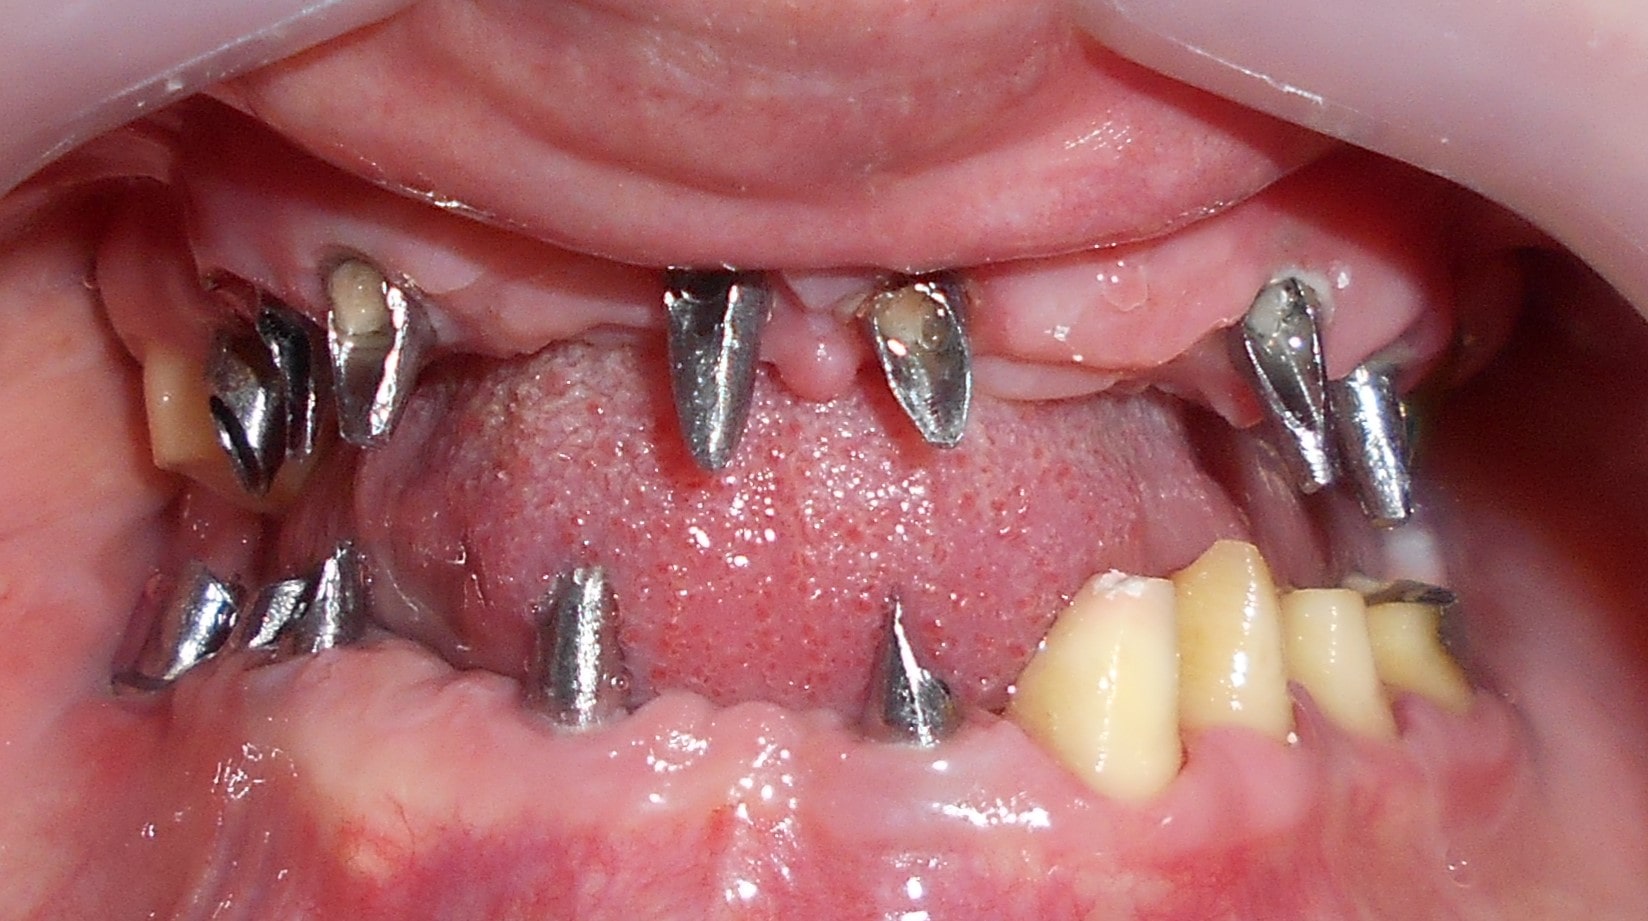

Pacijent dolazi sa starim mostovima i izraženom parodontopatijom u donjoj vilici. Urađeno je skidanje postojećih mostova i istovremena ekstrakcija svih parodontopatičhin zuba uz ugradnju sedam implantata u gornjoj vilici i pet implantata u donjoj vilici. Pacijent je nakon tri dana bio privremneo protetski zbrinut sa fiksnim privremeni krunicama koje su fiksirane na tek ugrađenim implantaima. Nakon četiri meseca je izrađen fiksni cirkonijum kermički- bezmetalni most u gornjoj i donjoj vilici. Rad uspešno završen pre tri godine.